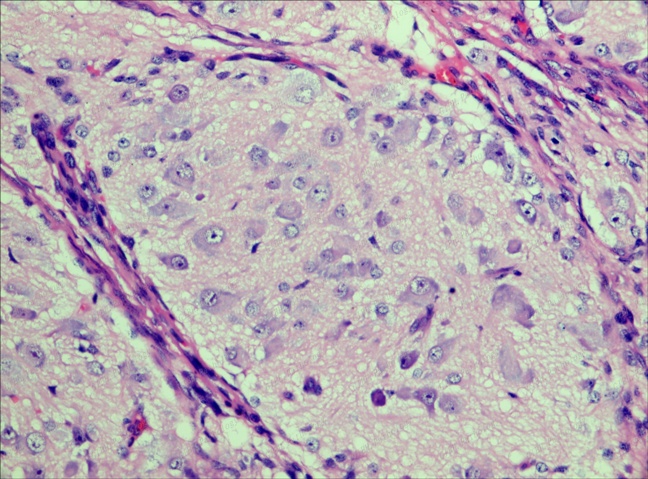

神經細胞